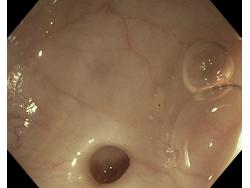

Uchyłki